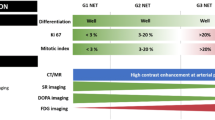

Neuroendocrine neoplasms (NENs) accounts for approximately 0.5% of malignancies, most commonly occurring in the gastrointestinal tract [1, 2]. Though most NENs have sporadic pathogenesis, in about 20% of cases, a familial component is recognized mainly in Multiple Endocrine Neoplasia type 1 (MEN1), Tuberous Sclerosis (TSC), Neurofibromatosis (NF) type 1, or Von Hippel Lindau (VHL) [3,4,5]. The overall incidence of NENs is approximately 5.86 per 100,000 per year, and 12–22% of tumors are metastatic at diagnosis [2, 3]. There was a nearly 6.4-fold increase in the prevalence of gastroenteropancreatic NENs (GEP-NENs) between 1975 and 2015, attributed to earlier detection and improved treatments with a resultant rise in survival [6]. The World Health Organization (WHO) established a set of pathological criteria to differentiate these two entities based on histologic differentiation, neuroendocrine marker expression, Ki-67 index, and mitotic activity [4, 7]. Establishing these diagnostic criteria has demonstrated a benefit in developing treatment strategies and improving the patient prognostication [8,9,10,11].

18F-FDG PET/CT is complementary to SSTR imaging in cases of high-grade and poorly differentiated GEP-NEN. It is typical for low-grade well-differentiated NENs to have little glucose metabolism, though, in 40% of these tumors, FDG uptake can be seen [54]. As dedifferentiation occurs, upregulation of glucose receptors and downregulation of SSTR occurs, termed a “flip-flop phenomenon” [4]. Significant inter and intra-tumoral variation occurs in patients with GEP-NENs. This led to the combined clinical use of both FDG and SSTR-PET to aid in characterizing tumor heterogeneity, risk stratification, and predicting tumor response to PRRT. A NETPET score was developed, combining imaging findings from 18F-FDG and SSTR-PET, which has shown promise as a prognostic biomarker and warrants investigation in future larger studies [55, 56].